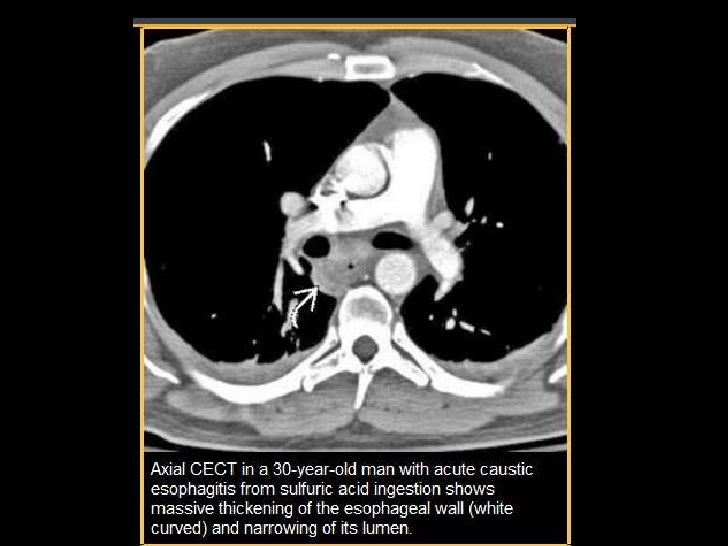

Pin on Chest Pain What Is Caustic Esophagitis Caustic ingestion can cause severe injury to the esophagus and the stomach. Caustic ingestion is defined as accidental or intentional ingestion of a corrosive substance that can cause severe injury to the. Esophagitis is inflammation in your esophagus, the swallowing tube that runs from your throat down to your. Esophagogastroduodenoscopy is an important and highly recommended diagnostic tool in the. What Is Caustic Esophagitis.